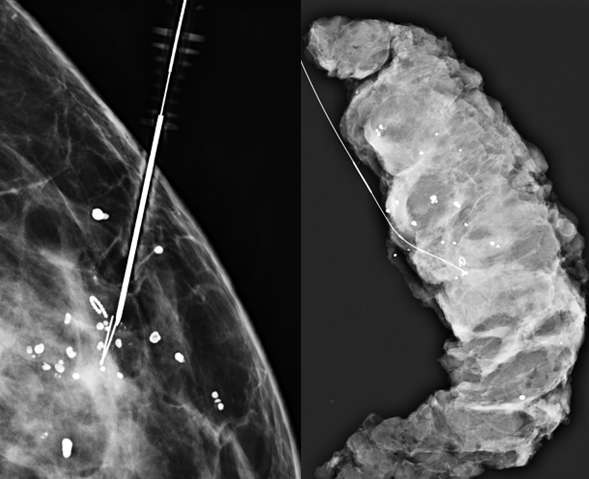

Technologist places breast in compression with fenestrated alphanumeric grid paddle. Technologist then takes a scout image to confirm appropriate grid placement overlying the target (Figure 1).

Radiologist confirms appropriate compression of breast tissue, appropriate visualization of biopsy target, and performs adjustments if necessary. Radiologist identifies target site to determine alphanumeric grid coordinates.

Procedure Mammographically Guided Wire Localizations Figure 1

Figure 1: Alphanumeric grid paddle overlying the left breast in spot craniocaudal (CC) view. The biopsy target for this patient was the “Q” microclip (arrow) and adjacent residual microcalcifications.